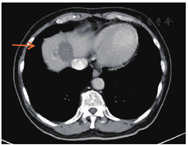

2012年7月起接受6次XELOX方案化疗,此后卡培他滨单药化疗1年;2013年7月影像学检查提示转移灶较前进展,肝脏出现新发转移灶;2013年9月16日针对肝转移瘤行射频消融术,2013年11月复查见肝Ⅷ段近膈顶处出现新病灶(图2)。2014年6月肺部CT未见明确转移灶,2014年11月右下肺考虑转移灶(图3)。2015年3月肺转移瘤较前进展,2015年3月起接受6个疗程FOLFIRI方案化疗(伊立替康150 mg/m2,ivgtt+氟尿嘧啶340 mg/m2,iv bolus+氟尿嘧啶2.2 g/m2,civ+亚叶酸钙330 mg/m2,ivgtt),2015年9月肝肺转移瘤均较前进展,2016年1月21日行肝转移瘤切除术,2016年2月胸部CT提示肺转移瘤进展,患者拒绝肺转移瘤介入治疗,2016年3月和4月行树突状细胞治疗。2017年3月肺CT:肺转移瘤增大,肝脏MRI肝Ⅷ段肿瘤存活(图4A),Ⅵ段新发转移癌(图4B)。2017年3月22日继续行FOLFIRI方案化疗,2017年4月—10月行10次西妥昔单抗+FOLFIRI方案化疗(伊立替康162 mg/m2,ivgtt+氟尿嘧啶365 mg/m2,iv bolus+氟尿嘧啶1.7 g/m2,civ+亚叶酸钙365 mg/m2,ivgtt+西妥昔单抗700 mg,ivgtt),2017年11月—2018年1月行5次西妥昔单抗单药(700 mg, ivgtt)靶向治疗,随访至2018年1月28日,生存时间超过94个月。